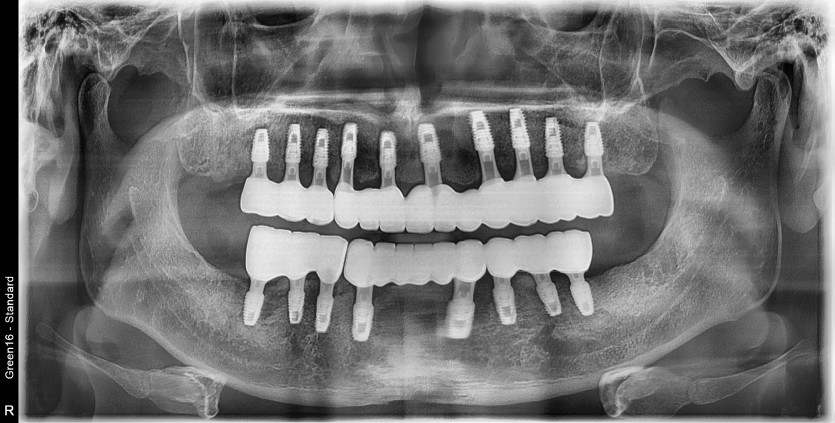

전체 임플란트 증례입니다.

18개의 임플란트로 완성하였습니다.